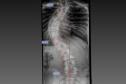

Estrutura e equipe: Paraná é referência em cirurgias de deformidade da coluna vertebral

Foto: Arquivo Pessoal